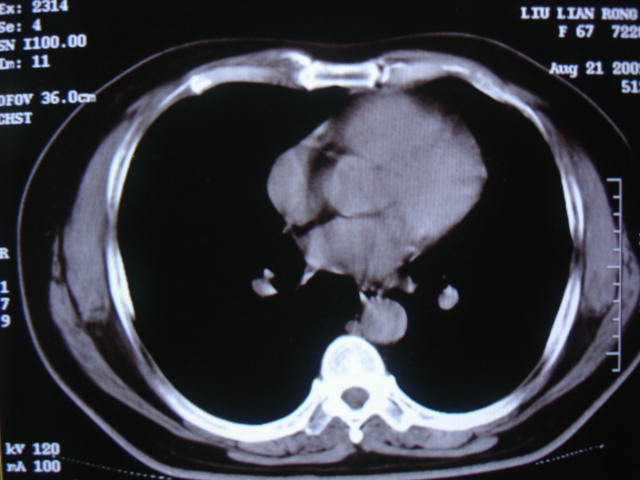

第一次ct2009.6.4

第二次ct2009.6.7 住院后ect未见异常,查痰(阴性)大量抗菌素抗炎一个月后病灶明显变小,7月5号出院后回家后口服抗菌素45天

第三次ct2009.8.21

病灶与胸膜成直边征,考虑炎症假瘤可能性大。

考虑左肺上叶炎症感染(炎性假瘤可能)。

考虑 左肺上叶炎症感染 [炎性假瘤可能性大]。

考虑左肺上叶炎症感染,以炎性假瘤可能性大。